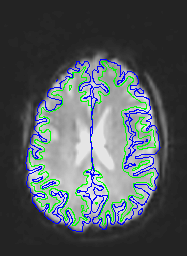

Here are uncorrected EPI images with the same boundaries overlaid.